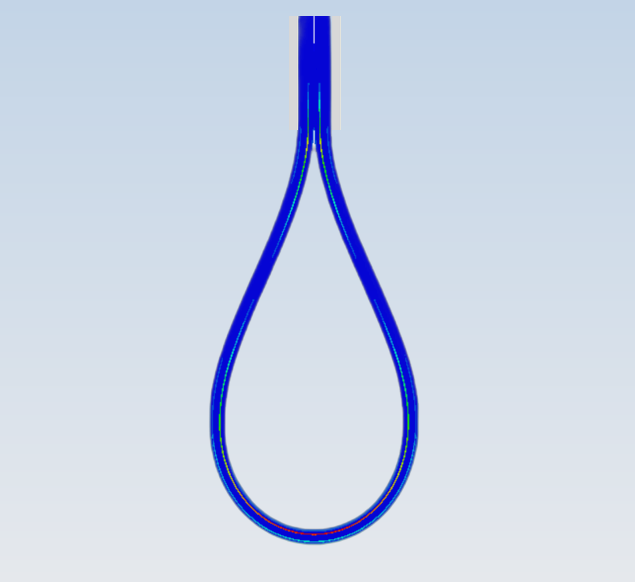

- 8 主动脉血流动力学仿真

流体 | 主动脉血流动力学仿真APP用于描述主动脉里的血流动力学情况。血液在主动脉里流动过程中,会根据血管形态改变流速与压力,沿途会有部分血液进入分支血管。主动脉血流动力学仿...